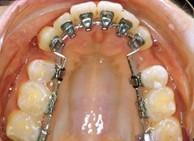

陶瓷托槽口內相(5)舌側矯治技術托槽

托槽放置於牙齒舌側,克服了唇側托槽暴露於外的缺點,隱形而不影響美觀,但其增加了醫師的操作難度,延長了椅位時間,且舒適度不及唇側矯治器,也在一定程度上影響了咀嚼發音等。